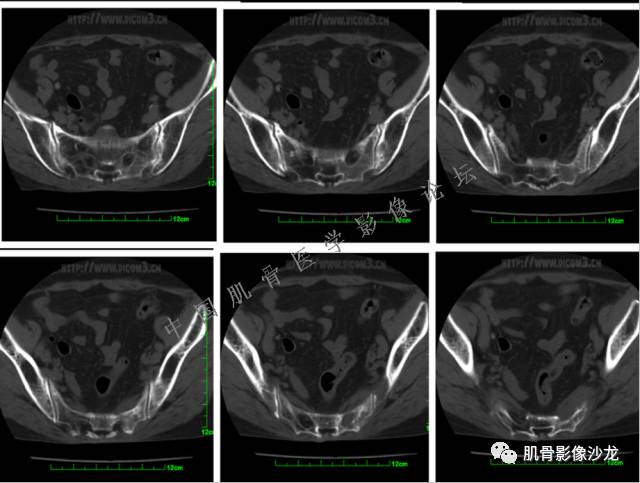

患者2月前无明显诱因下感右腿疼痛、麻木,疼痛呈持续性,发作时无法行走,休息后可缓解。当时无明显肿块,患者遂至当地医院就诊,查X片见右髂骨骨质破坏。6周前患者自觉右髋部渐大肿块,初肿块较小,后肿块逐渐增大,现肿块约12*10cm大小,有压痛。患者遂至我院就诊,查MRI:右髂骨异常信号,伴软组织肿块。ECT、肺CT未见转移。现患者为求进一步治疗,门诊拟“右髂骨肿块 ”收治入院。 患者发病来,神清,精神可,胃纳夜眠可,二便无殊,体重无明显变化。

1、软骨肉瘤可以有膨胀性骨质破坏(病例3,4),可以有溶骨性骨质破坏(病例2),局部皮质因为破坏变薄,中断 ;

2、软骨基质T2WI高信号,软骨小叶分叶状,也就会出现高老师提到的骨内膜扇贝形压迹。一般认为骨内膜扇贝形压迹超过骨皮质厚度的2/3是软骨肉瘤在长管状骨的特征性表现。如上图。3、软组织肿块或肿胀;

4、 钙化,环形,弓形,边缘模糊 ;

5、增强后进行性延迟,不均匀分割状强化, 会强化的纤维间隔,软骨小叶不会强化,关于老师们说到的钙化,软骨肉瘤不一定会有钙化 。

2、软骨肉瘤的发病部位排名:最好发部位为髂骨,其次股骨、肱骨和脊柱。